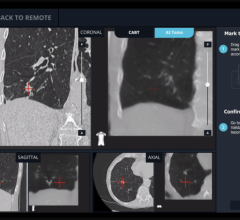

Founded in 2007, Therenva supports physicians in planning and performing minimally invasive endovascular interventions through innovative imaging solutions. The current portfolio includes EndoSize and EndoNaut, a patented solution for intra-operative 3-D navigation and localization of devices providing more confidence, accuracy, and visual comfort during catheterization procedures.

By bundling the leading C-arms of Ziehm Imaging and the EndoNaut solution, physicians already benefit from advanced 3-D intra-operative navigation for optimal guidance in endovascular interventions.

“Joining forces with Ziehm Imaging as innovation leader in mobile C-arm technology is a great opportunity for us to make our software devices available to physicians globally,” said Cemil Göksu, Co-founder and CEO of Therenva. “A deeper soft- and hardware integration will allow us to develop solutions that will set new standards in image fusion and 3-D navigation to provide clinicians with powerful yet seamless workflows supporting their patients’ treatment.”

Therenva has designed advanced and user-friendly imaging software toolsets for cardiovascular procedures since 2007. The unique EndoSize 3D case planning software has become an essential tool in the daily practice of many physicians and healthcare professionals. By widening the skills of the users and their abilities to plan cases quickly and accurately, EndoSize saves time and improves patient care.